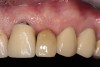

After 2 weeks, excellent soft-tissue healing and maintenance of the labial gingival tissue was evident. The same was true after 3 months (Figure 21). The gingival zenith continued to be maintained after 1.5 years (Figure 22). Importantly, the facial wall bone thickness of the implant also was maintained at the 1.5-year follow-up (Figure 23), suggesting favorable maintenance of this case.

Fig 22. Final restoration after 1.5 years. Note the soft-tissue contour on the buccal aspect.

Figure 22